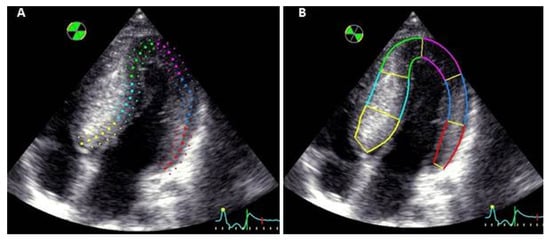

3.3. Myocardial Deformation

3.4. Assessment of Regional Longitudinal Strain